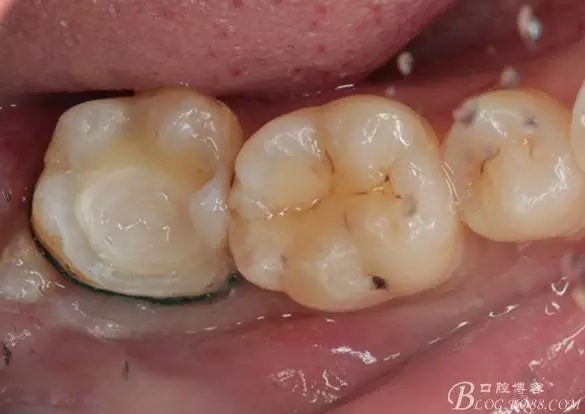

第四次復(fù)診,37叩(—)。此次行冠部修復(fù),因涉及38的拔除,患者不愿拔除,與患者介紹修復(fù)材料與方法,擬37E.max嵌體修復(fù),術(shù)前常規(guī)簽修復(fù)知情同意書。

去除暫封物,拍照,比色。

流動(dòng)樹(shù)脂充填窩洞,金霸王車針和鎢鋼車針常規(guī)備牙,配合硅膠尖拋光,頰側(cè)排00排齦線。硅橡膠二次法取模,記錄咬頜關(guān)系,臨時(shí)樹(shù)脂充填窩洞。

一周后復(fù)診,37臨時(shí)充填物完好。去除臨時(shí)充填物,清潔基牙,試戴嵌體,就位良好,邊緣密合。取下嵌體,常規(guī)處理,9.5%HF處理20S,沖洗一分鐘,95%酒精蕩洗5分鐘?;劳磕?7%的磷酸凝膠,釉質(zhì)區(qū)域酸蝕30S,本質(zhì)區(qū)域15S。粘固用的是3M第八代粘接劑套裝,照說(shuō)明書逐步操作。最終固化時(shí)涂滿阻氧劑,每個(gè)牙面最少光照30S,光固化燈用漸強(qiáng)模式。常規(guī)調(diào)合,配合硅膠尖套裝拋光。術(shù)后常規(guī)醫(yī)囑,不適隨診。